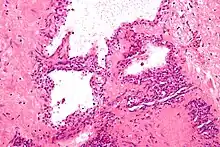

Micrograph showing a pancreatic serous cystadenoma, a type of cystadenoma. H&E stain.